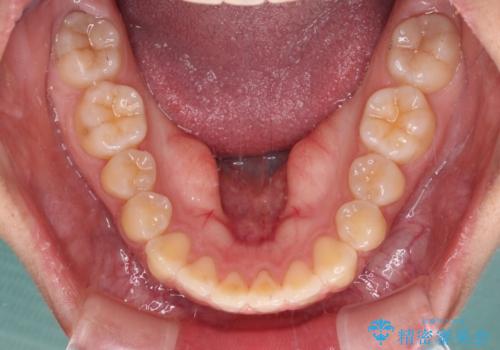

カリエールディスタライザーを併用したことで、確実かつ短期間で治療を終えることができました。